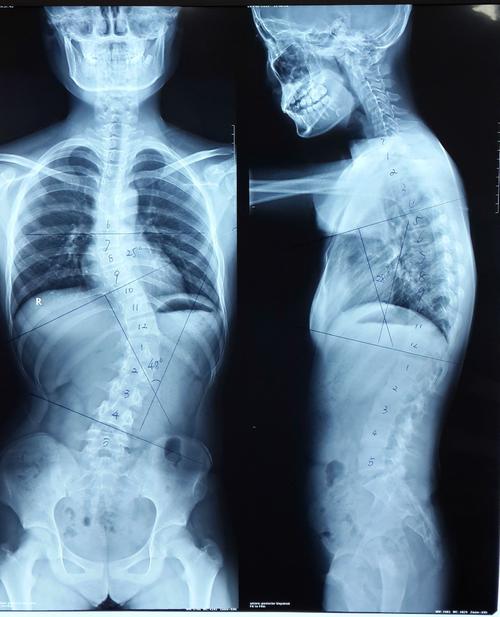

从2020年开始,康复科医师和治疗师组成的筛查小组开始对学生们进行AIS(青少年特发性脊柱侧弯)筛查及问卷调查。每年大约有9万人接受筛查。对于筛查阳性的学生,门诊医师会进一步完善脊柱全长正侧位摄片,测量Cobb角(测量侧弯曲角度的方法,用于评估脊柱侧弯的严重程度),并明确诊断。根据侧凸程度分级管理及定期随访,力求早发现、早预防、早治疗。目前,已完成学生前期筛查工作。徐汇区青少年特发性脊柱侧凸发病率约为3%,高于国内外文献数据。